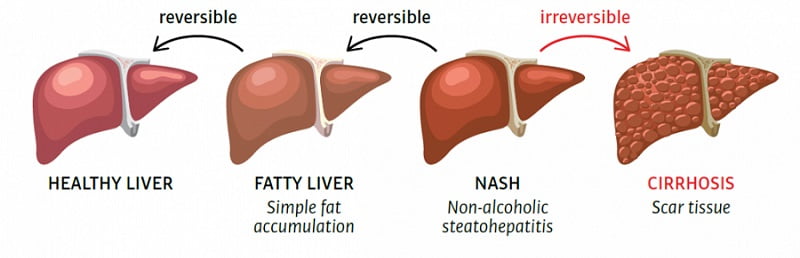

Картинки с надписью Liver: Как выбрать и использовать